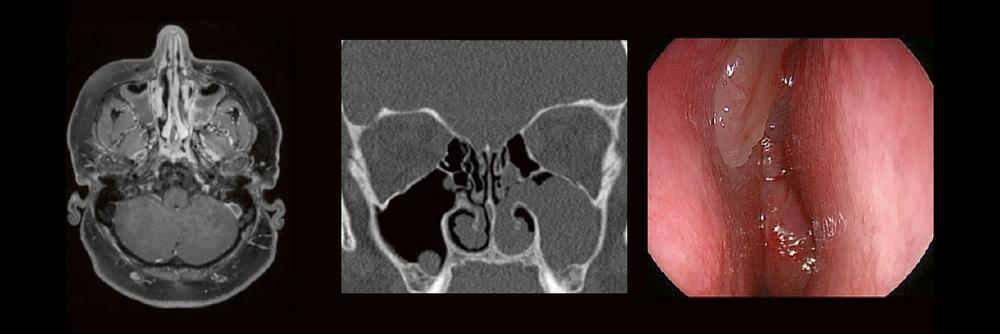

Professor Dr. med. Marc Brockmann WEITERENTWICKLUNGEN VON KOPF BIS FUSS BEIM VC Oberstarzt Dr. med. Stephan Waldeck DEEP-LEARNING-REKONSTRUKTION IN DER NEURORADIOLOGIE Die CT ist ein essentielles Routine-Verfahren in der Neuroradiologie. Bei steigender Bildqualität konnte die Röntgendosis mit neuen Technologien in der letzten Dekade deutlich gesenkt werden, was für die zielgerichtete und möglichst schonende Behandlung von…